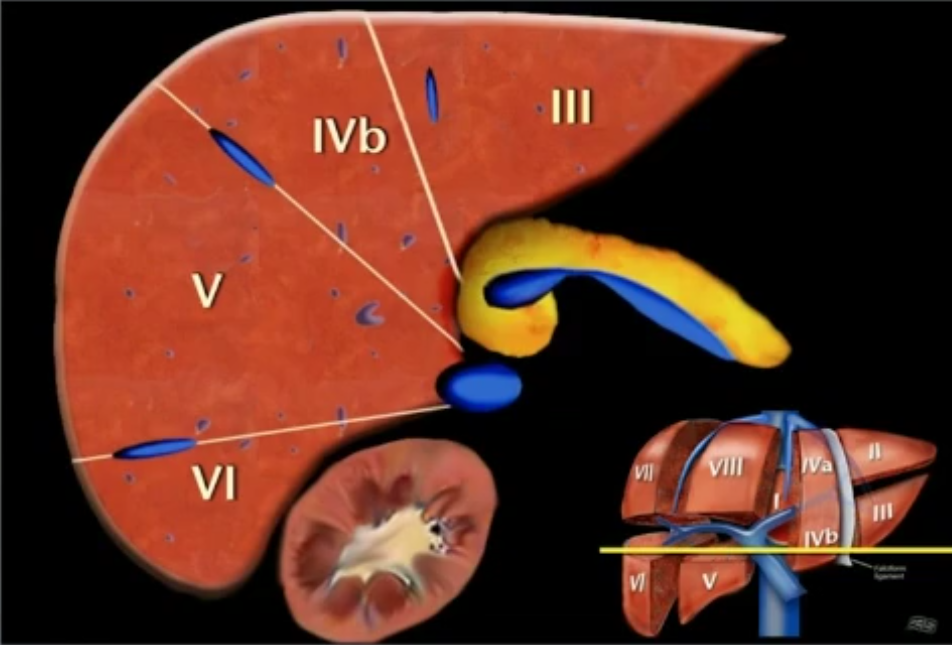

bismuth分段

- 纵向中肝静脉分左右,右肝静脉分右前后,镰状韧带分左内外

- 从右到左:右肝后(右肝静脉)右肝前(中肝静脉)左肝内(镰状韧带)左肝外

- 纵向门静脉左右支分上下两份

中心1,其他顺时针标号

解剖标记

- 第一肝门上方中肝静脉,右肝静脉

- 门静脉左支分左肝上下

- 门静脉右支分右肝上下

- 顺时针在片子里是左到右